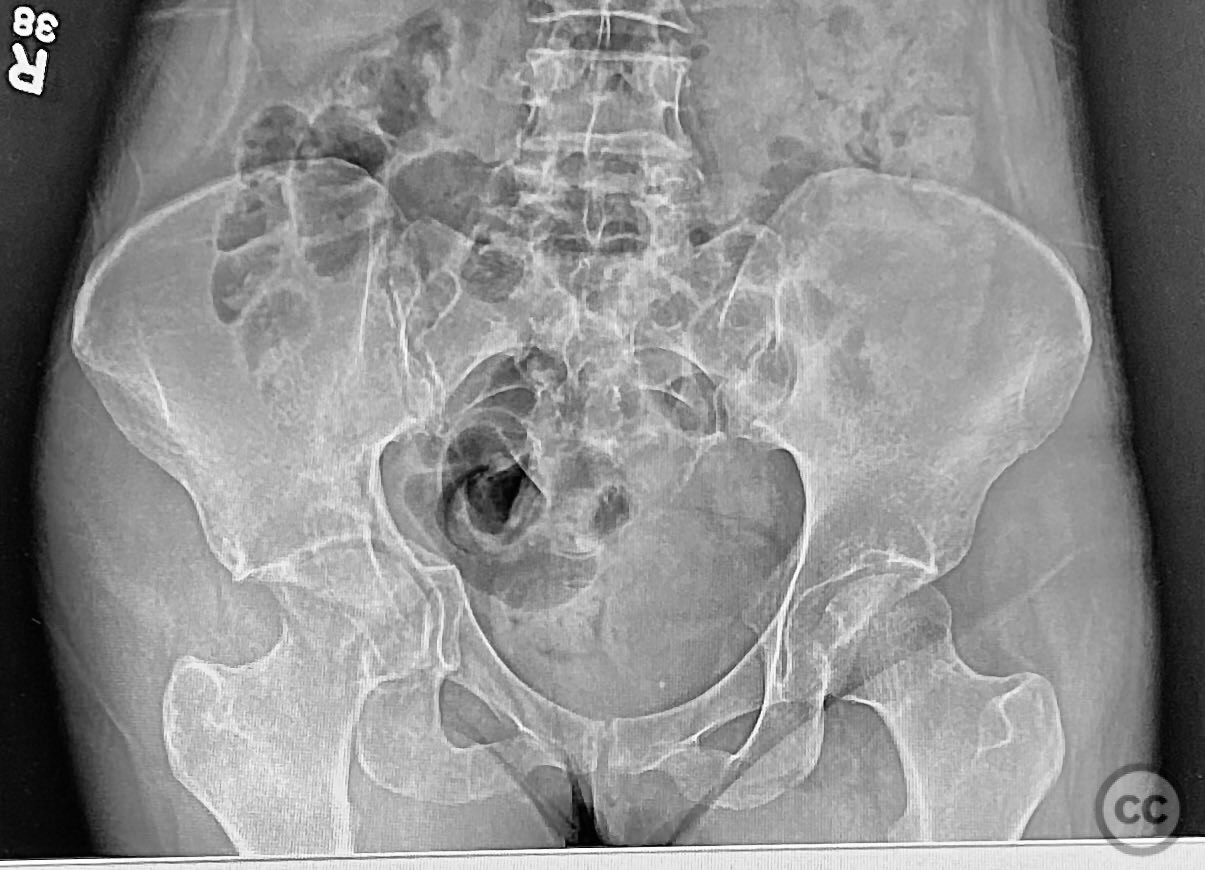

Acetabulum - AO/OTA 62x